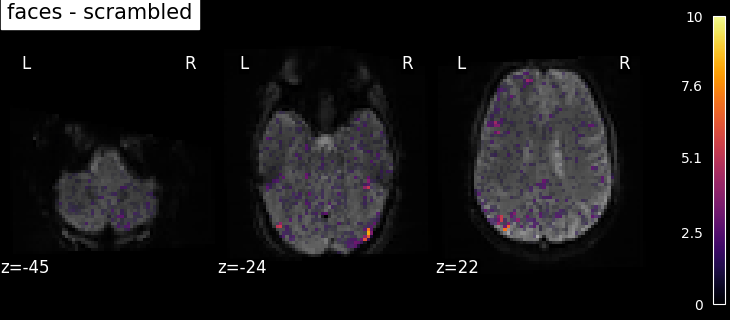

To get more interesting results out of the GLM model, contrasts can be computed between regressors of interest. The nilearn.glm.first_level.FirstLevelModel.compute_contrast function can be used for that. First, the contrasts of interest must be defined. In the spm_multimodal_fmri dataset referenced above, subjects are presented with ‘normal’ and ‘scrambled’ faces. The basic contrasts that can be constructed are the main effects of ‘normal faces’ and ‘scrambled faces’. Once the basic_contrasts have been set up, we can construct more interesting contrasts like ‘normal faces - scrambled faces’.

The activation maps from these 3 contrasts is presented below:

../_images/sphx_glr_plot_spm_multimodal_faces_002.png ../_images/sphx_glr_plot_spm_multimodal_faces_003.png ../_images/sphx_glr_plot_spm_multimodal_faces_004.png